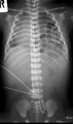

Image

37.a.

37.b.

37.c.

37.d.

37. a-d) X-ray of the right humerus. a. Rarefaction in the proximal-medial part of metaphysis of the right humerus – early osteomyelitis. b. Two weeks after the lytic area has grown. c. 1 month later sclerotic regeneration has begun. d. 4 months after almost complete healing. Osteomyelitis, infant.